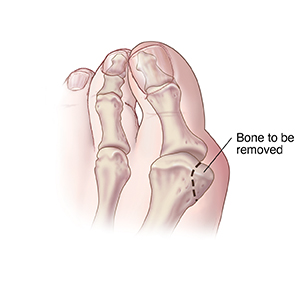

Head chevron osteotomy

The first metatarsal bone is cut. Its head is moved closer to the second metatarsal bone. A screw or pin can be used to hold the first metatarsal bone in position. The bony bump is also removed. You will need to wear a surgical shoe or boot for a few weeks. This is to protect your foot while healing.